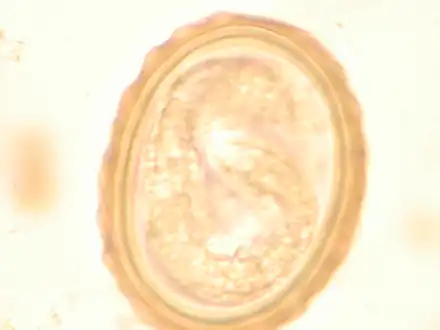

Most diagnoses are made by identifying the appearance of the worm or eggs in feces. Due to the large quantity of eggs laid, diagnosis can generally be made using only one or two fecal smears.[31] The diagnosis is usually incidental when the host passes a worm in the stool or vomit. The eggs can be seen in a smear of fresh feces examined on a glass slide under a microscope and there are various techniques to concentrate them first or increase their visibility, such as the ether sedimentation method or the Kato technique. The eggs have a characteristic shape: they are oval with a thick, mamillated shell (covered with rounded mounds or lumps), measuring 35–50 micrometer in diameter and 40–70 in length. During pulmonary disease, larvae may be found in fluids aspirated from the lungs. White blood cell counts may demonstrate peripheral eosinophilia; this is common in many parasitic infections and is not specific to ascariasis. On X-ray, 15–35 cm long filling defects, sometimes with whirled appearance (bolus of worms).